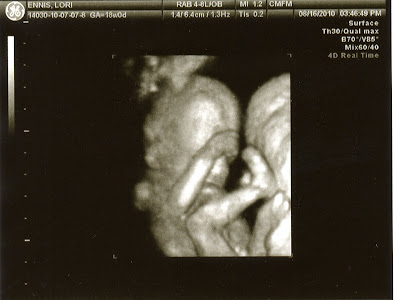

Luke was pretty chill yesterday. Actually, it was more that he was sleeping off the all-nighter he'd pulled the night before. He was measuring 19w6d (which is just perfect as I was 20w0d) and a respectable 11 oz. He definitely looks like he's filling out some! He was practicing some yoga, avoiding pictures, and swallowing amniotic fluid quite a bit to get those little lungs good and mature.

Here are some of the most recent pics of my boy.  He's quite Bad To The Bone, if I say so myself!

Knees to nose...to have that flexibility again...(or ever!)

This is his Fonzie Thumbs Up!  "Ehhhhh"

I hear my mommy has a thing for sweet feet!!